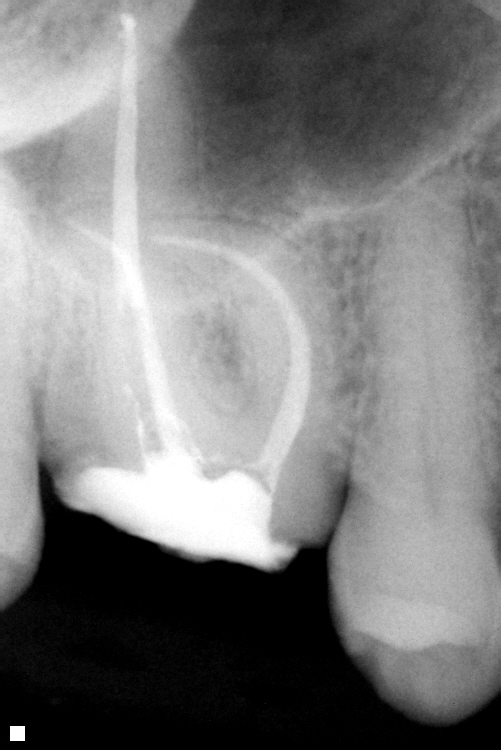

This is a root canal for a first maxillary molar (tooth #3) where an old crown (over 10 year old crown) fell out due to decay around the margin. As you can see there was a very curved canal which required additional time for proper root canal treatment. This tooth will now be restored with a post and crown allowing the patient to keep the tooth.